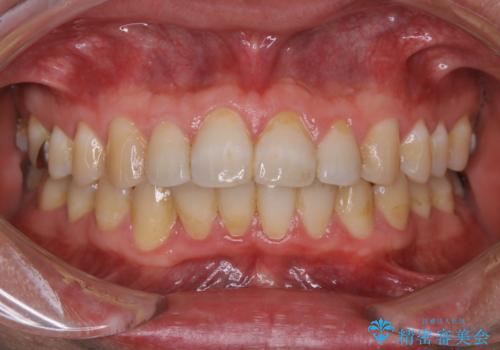

全体的にプラークや歯石が付着していて、歯肉炎が見られました。

状態に合った専門的な器具を使用して、歯質や歯肉へのダメージを抑えながらPMTC(自費クリーニング)60分コースを行いました。矯正治療後の保定装置がワイヤーの場合、フロス・糸ようじが通せないこと、歯ブラシがしずらいことなどにより、歯石プラークなどが付着しやすくなります。そのため専門的な器具による細かいケアを行うことがとても大切です。